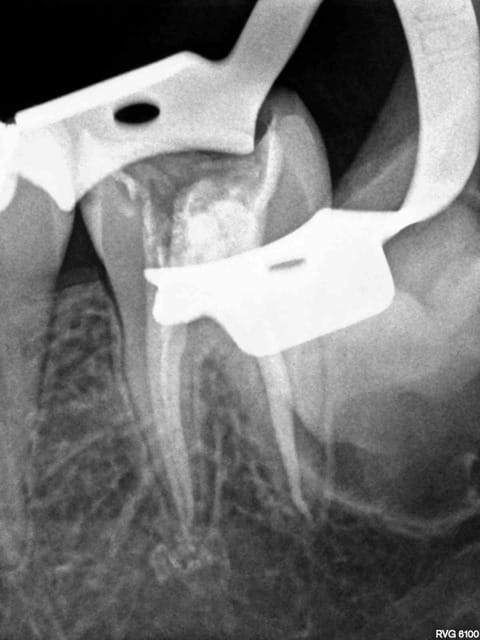

tient un boulot ou il y a un peu de tout.

bridge antérieur , car la pose d'implants nécessitait de la reconstruction trop importante, endo couronne sur les molaires mandibulaires par manque de hauteur, onlay. implants à la mandibule.

A noter les 2 PM maxillaires qui comportaient

chacune 3 canaux.